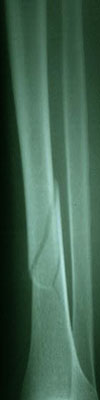

Fraktur tulang adalah cedera serius yang sering terjadi akibat berbagai kecelakaan atau aktivitas fisik yang berlebihan. Identifikasi fraktur tulang dengan cepat dan tepat sangat penting untuk menentukan perawatan yang sesuai. Salah satu pendekatan untuk mengidentifikasi fraktur tulang adalah melalui analisis citra radiografi. Dalam artikel ini, akan dijelaskan bagaimana pengolahan citra, khususnya dengan metode deteksi tepi Canny dan ekstraksi ciri menggunakan metode moment invariant, dapat digunakan untuk identifikasi fraktur tulang tibia dan fibula dengan bantuan algoritma Support Vector Machine (SVM).

Langkah pertama dalam identifikasi fraktur tulang adalah mendapatkan citra radiografi dari daerah yang terkena dampak. Citra radiografi ini biasanya diambil dengan menggunakan peralatan medis yang sesuai.

Deteksi tepi adalah langkah kunci dalam identifikasi fraktur. Metode deteksi tepi Canny adalah salah satu teknik yang umum digunakan untuk menemukan tepi dalam citra. Ini bekerja dengan mengidentifikasi perubahan tajam dalam intensitas citra, yang sering terjadi di sekitar tepi objek. Hasil dari langkah ini adalah citra dengan tepi yang lebih tajam dan jelas.